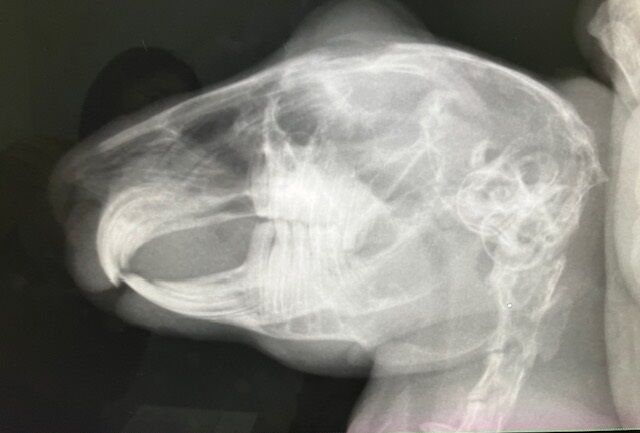

術前検査のレントゲン

特に問題ありません。

※クリックで拡大見れます。

切歯もキレイ